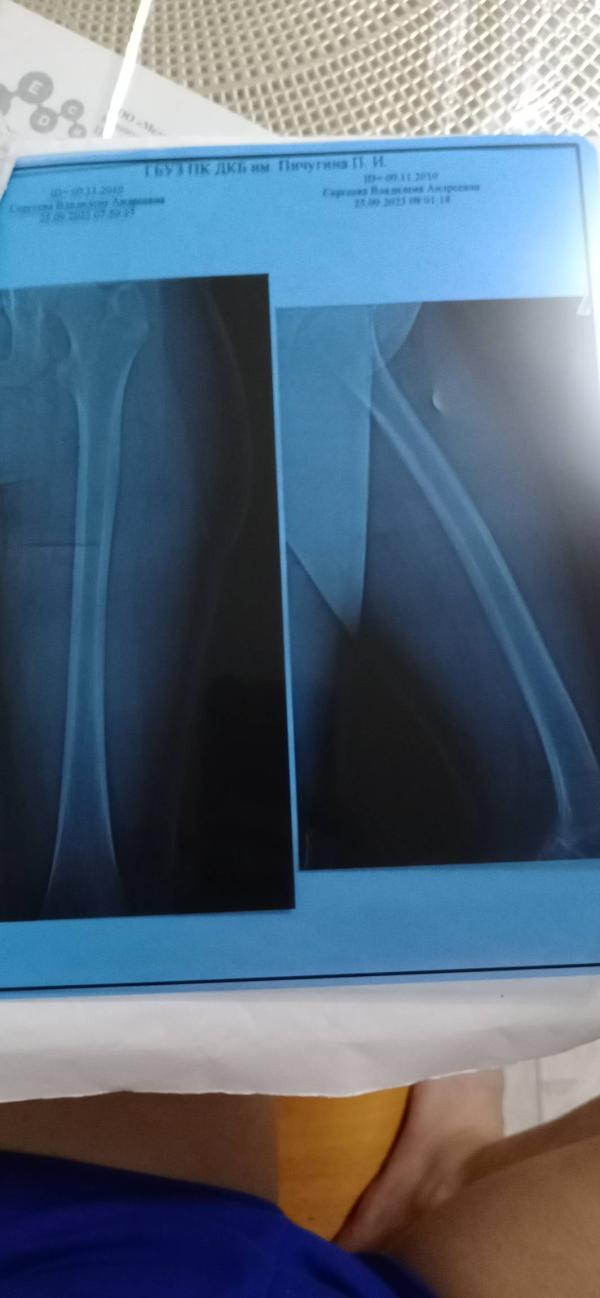

Сходили мы на УЗИ и даже два, на ренген.

И честно сказать были удивлены, а даже шокированы. У Влады оказывается был перелом, а что это за образование в виде шишки ни кто незнает.

Ну дак вот он смотрел, щупал, крутил и рассматривал очень внимательно дочь. И предположил что у неё приударе оторвалась мышца , но не факт.